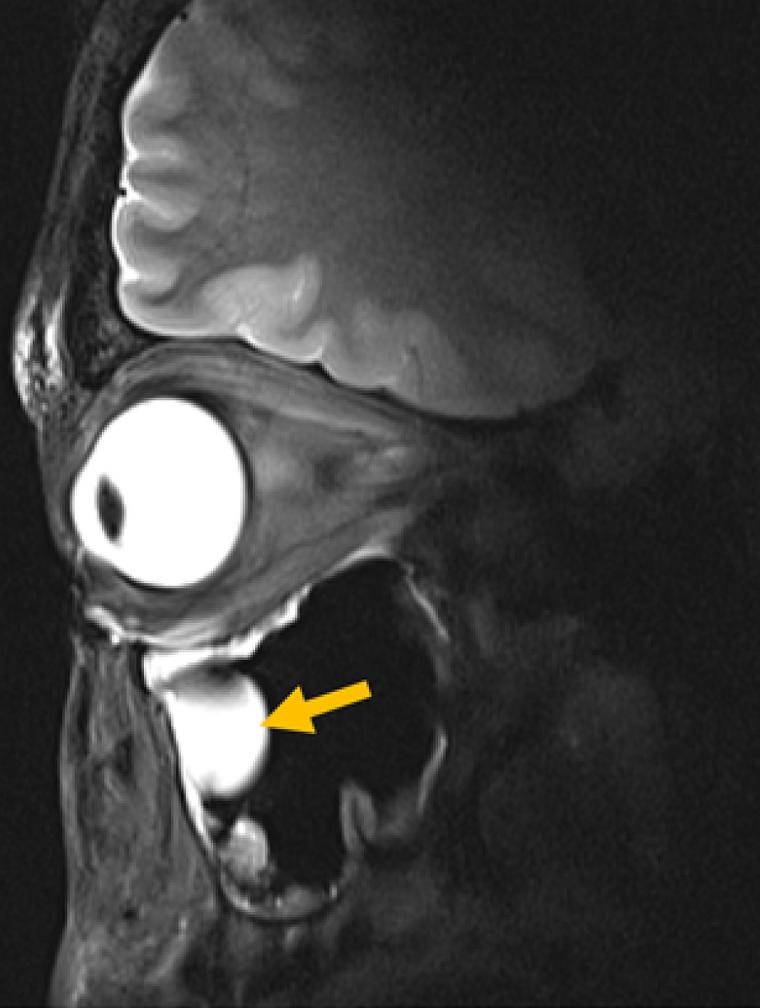

Entscheidend für die klinische Praxis ist zudem, dass die Antenne in bestehende MRT-Systeme passt, sodass keine neue Infrastruktur erforderlich wird. Validiert haben die Wissenschaftler ihre Technologie anhand von MRT-Bildern des Auges, der Augenhöhle und des Gehirns bei einer Gruppe von Freiwilligen. Niendorf und sein Team arbeiteten dabei eng mit Forschern des Universitätsklinikums Rostock zusammen und kombinierten so Expertise in MRT-Physik mit klinischer Ophthalmologie und translationaler Bildgebung.

Die Forscher konnten zeigen, dass ihr System für den routinemäßigen klinischen Einsatz geeignet ist. „Wir sehen eine klare Relevanz für Anwendungen in der Augenheilkunde. Die neue Technologie ermöglicht anatomisch detaillierte MRT-Bilder des Auges mit hoher räumlicher Auflösung und Weichteilkontrast“, sagt Prof. Oliver Stachs, Koautor der Publikation von der Universitätsmedizin Rostock. „Sie öffnet die Sicht auf (patho)physiologische Prozesse, die bislang weitgehend unzugänglich waren.“